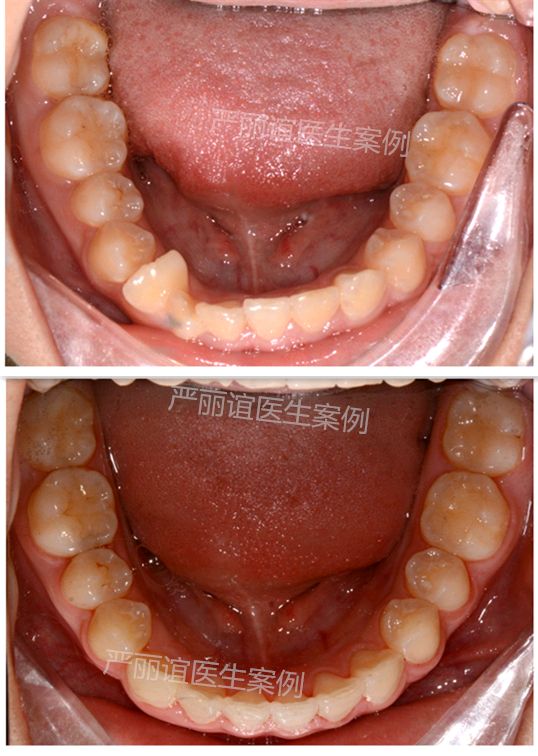

这个患者上颌两个小虎牙外凸,下颌一个畸形过大牙,自觉很影响颜值,想通过矫正改善。

检查发现她上颌最后还有一定的骨量,加上两个小虎牙外凸不是特别严重,需要2-3mm就可以排齐。下颌的畸形过大牙外面的保护层比其他牙齿厚,沟通后选择了上颌推磨牙远移,下颌片切的矫治方案。

一年半时间,矫正结束前后对比图如下。